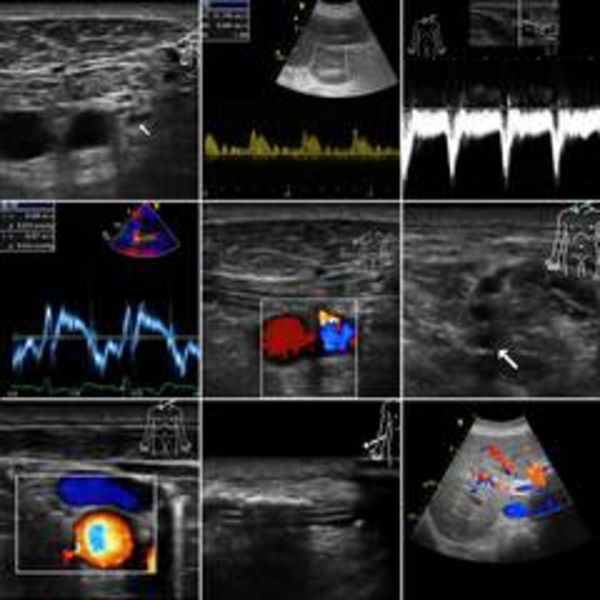

Die Entwicklung ultraschall-gesteuerter Punktionen sowie der perioperativen Ultraschalldiagnostik ist rasant. So ist es verständlich, dass die Ausbildung in der Ultraschalldiagnostik und der ultraschall-gesteuerten Punktionen für Anästhesistinnen und Anästhesisten eine wachsende Bedeutung einnimmt. Dies spiegelt sich auch in den Fachgesellschaften wider, die der Ausbildung einen immer höheren Stellenwert beimessen.

Aus dieser steigenden Bedeutung der Sonografie für Anästhesisten und Intensivmediziner erwächst die Verpflichtung, didaktische Konzepte zu entwickeln, um eine erfolgreiche Vermittlung des komplexen Wissens zu gewährleisten. Der inhaltliche Rahmen ist durch den Anforderungskatalog der DEGUM (Deutsche Gesellschaft für Ultraschallmedizin) sowie der DGAI (Deutsche Gesellschaft für Anästhesiologie und Intensivmedizin) vorgegeben.

Wichtig ist dem Veranstalter, der Klinik und Poliklinik für Anästhesiologie und operative Intensivmedizin, eine didaktische Ausrichtung des Kurses mit einem starken Praxisbezug und einem hohen Anteil von praktischen Übungen.